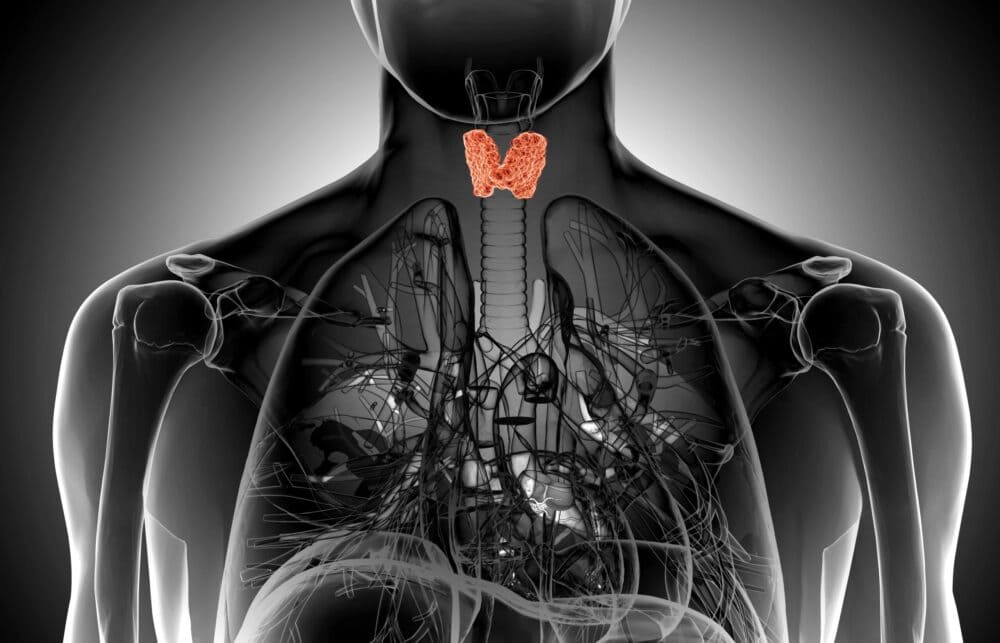

Hausarzt und Schulmedizin, Thema Hashimoto

Ich kann das alles nur voll bestätigen. Die Liste meiner Erkrankungen ist lang, ob sie jetzt (bzw. das gesamte Elend) mit Hashimoto begann, weiß ich nicht; hinzu kamen dann u.a. glutensensivitive Enteropathie (die Zöliakiediagnose haben meine Ärzte versaut), unzählige Allergien und Unverträglichkeiten, Neurodermitis und / oder Psoriasisarthritis (da waren sich die Rheumatologen nicht so einig) und mehrfach Fibromyalgie. Ich erfülle aber auch alle Bedingungen zu CFS, chronische Erschöpfung seit vielen Jahren.

Natürlich fühlt sich das an wie eine Schilddrüsenunterfunktion. Wenn ich im Netz die Symptome für eine solche heraussuche, erfülle ich diese Symptome alle.

Also die gesamte Hormonproblematik, die ja bekanntermaßen u.a. von der Schilddrüse gesteuert wird, damit wird man in Deutschland, wenn man Kassenpatient ist, alleine gelassen.

Die freien Schilddrüsen-Werte waren grenzwertig, der eine war in Ordnung, der andere m.Meinung nach zu niedrig (fT4), aber auch das sah die Ärztin anders. Komisch, daß Ärzte immer besser wissen, wie es einem mit welchen Werten geht. Es kann auch eine Umwandlungsstörung vorliegen da der TSH so knapp über Null lag. Aber von Umwandlungsstörung haben die bestimmt auch noch nie was gehört. Auf jeden Fall bin ich laut dieser Ärztin optimal eingestellt, die anderen Hormonmängel hat sie gar nicht beachtet.